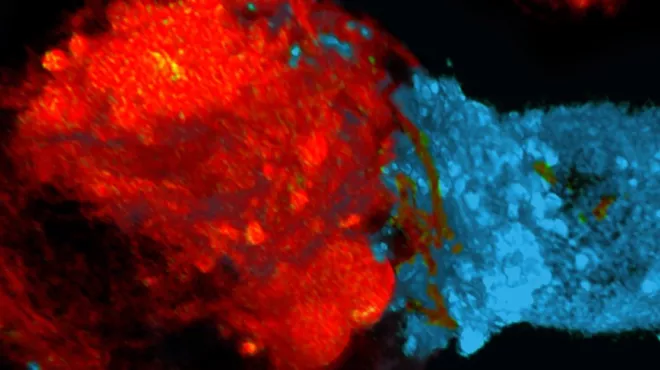

Celle- og genterapier bygger på grundig forskning, der bygger på mange årtiers videnskabelige fremskridt. De centrale redskaber og teknologier er blevet afprøvet og raffineret af utallige eksperter – først i laboratoriet og sidenhen i klinikken. Ved celleterapi dyrkes eller modificeres cellerne uden for kroppen, før de indsprøjtes i patienten, hvor de udvikler sig til et "levende lægemiddel". Ved genterapi udskiftes, inaktiveres eller indføres generne i celler – enten uden for eller inde i kroppen – for at behandle en sygdom. Nogle behandlinger kvalificerer sig som både celle- og genterapier.

Den enkelte celle- og genterapi udvikles på grundlag af detaljeret information om årsagerne til en patients sygdom. Den behandler en tilstand eller sygdom ved kilden ved på genniveau at reparere eller forbedre celler. Hos Novartis samarbejder vi inden for celle- og genterapi for at bringe denne revolutionerende behandlingsform til patienter med en lang række sygdomme, herunder genetiske sygdomme og visse livstruende kræftformer.